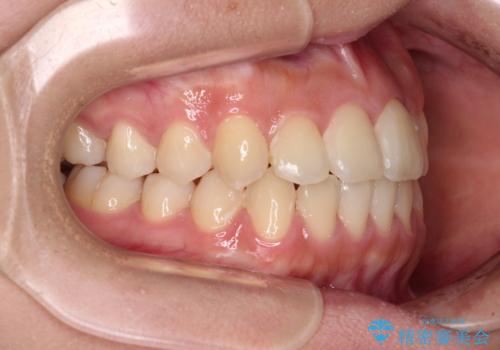

前歯のクロスバイトを短期間で解消 目立たないワイヤー矯正

- 前歯のクロスバイトを治したいとのことで来院された患者様です。

できる限り楽して、短期間で治したいとのことで、ワイヤー装置にて矯正治療を行うこととしました。